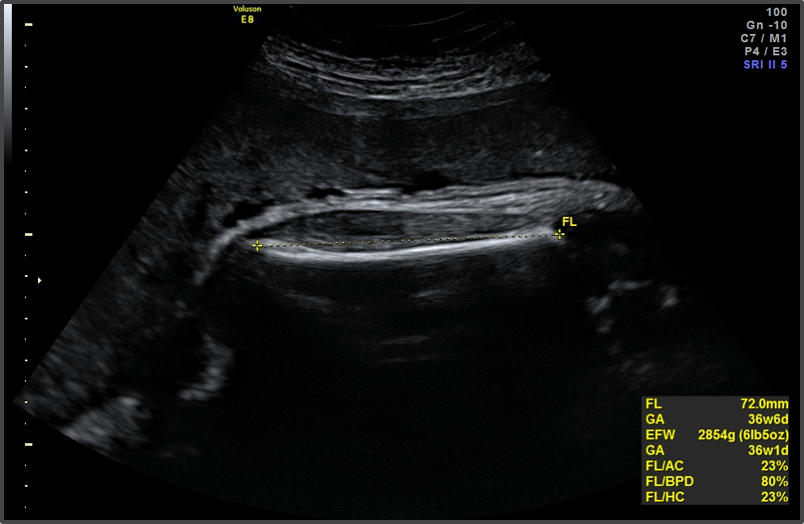

Your baby is the size of a papaya.

Approx Baby Weight: 2.6kg

Approx Baby Size: 47.4 cm

Baby Development

The baby’s body is fully formed and it’s getting ready for delivery.